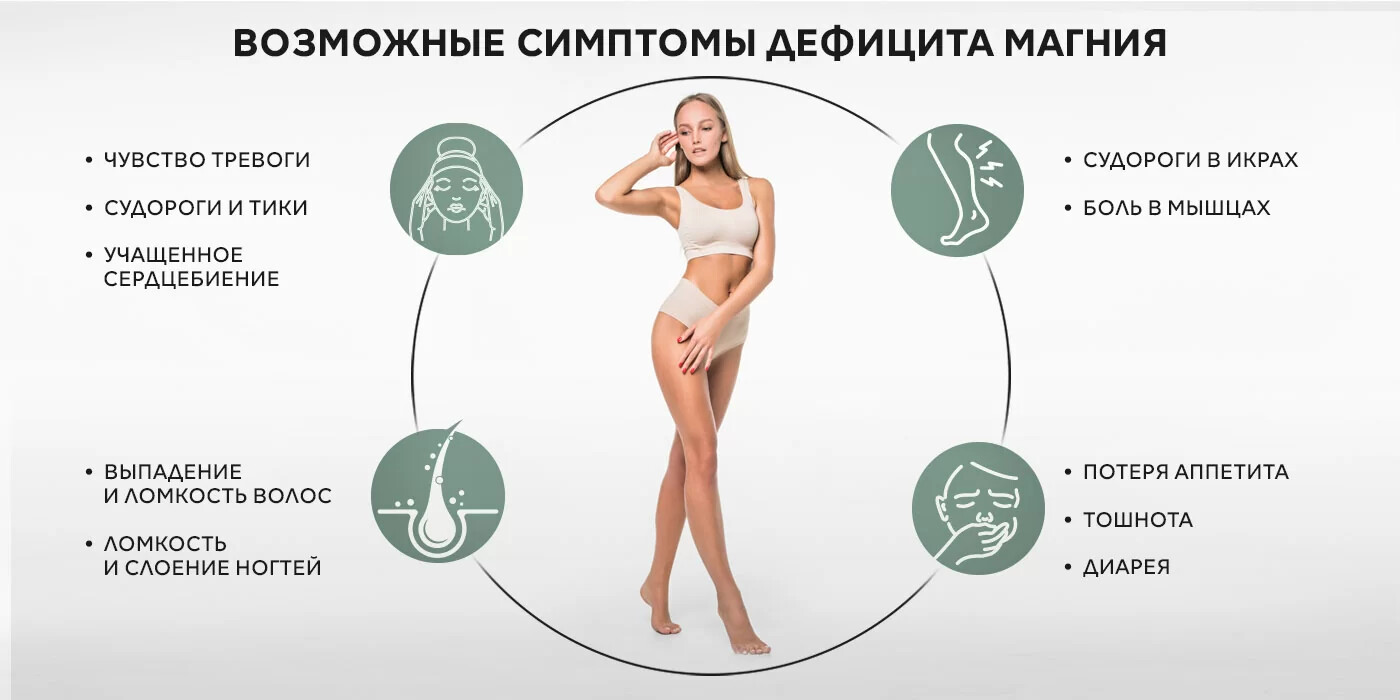

Макроэлементы и микроэлементы Магний, как и калий, участвует в передаче нервных импульсов. Дефицит магния в организме вызывает раздражительность, нервозность и депрессию. Магний управляет ключевым рецептором в гиппокампе, важным для функции обучения и памяти. Достаточное его количество – непременное условие обеспечения нейропластичности головного мозга. Магний важен для основного рецептора, получающего возбуждающий нейромедиатор – глутаминовую кислоту. Магний помогает рецептору открыться для ее приема, что повышает эффективность синаптических связей.

Магний, как и калий, участвует в передаче нервных импульсов. Дефицит магния в организме вызывает раздражительность, нервозность и депрессию. Магний управляет ключевым рецептором в гиппокампе, важным для функции обучения и памяти. Достаточное его количество – непременное условие обеспечения нейропластичности головного мозга. Магний важен для основного рецептора, получающего возбуждающий нейромедиатор – глутаминовую кислоту. Магний помогает рецептору открыться для ее приема, что повышает эффективность синаптических связей.